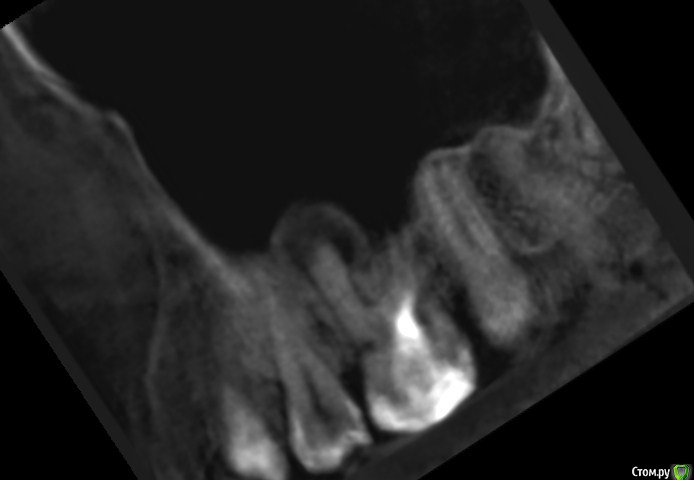

Подскажите, пожалуйста, точно удалять? Как принять это решение, все таки надежда на какой то другой лечебный вариант теплится =)post-59509-0-08196600-1578493080_thumb.jpgpost-59509-0-63211400-1578493088_thumb.jpgpost-59509-0-77705800-1578493096_thumb.jpgpost-59509-0-02698500-1578493106_thumb.jpgpost-59509-0-04880900-1578493120_thumb.jpgpost-59509-0-11411000-1578493128_thumb.jpg

По представленным срезам создаётся впечатление, что лечение вполне возможно